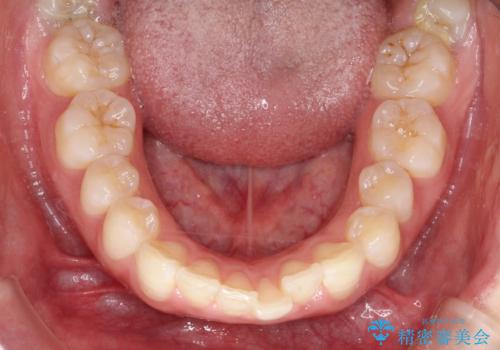

上下左右の歯を1本ずつ、合計4本抜歯しして前歯を後方に下げて、口元の突出感を改善する計画としました。

前歯をしっかり下げることで、口元がすっきりしました。